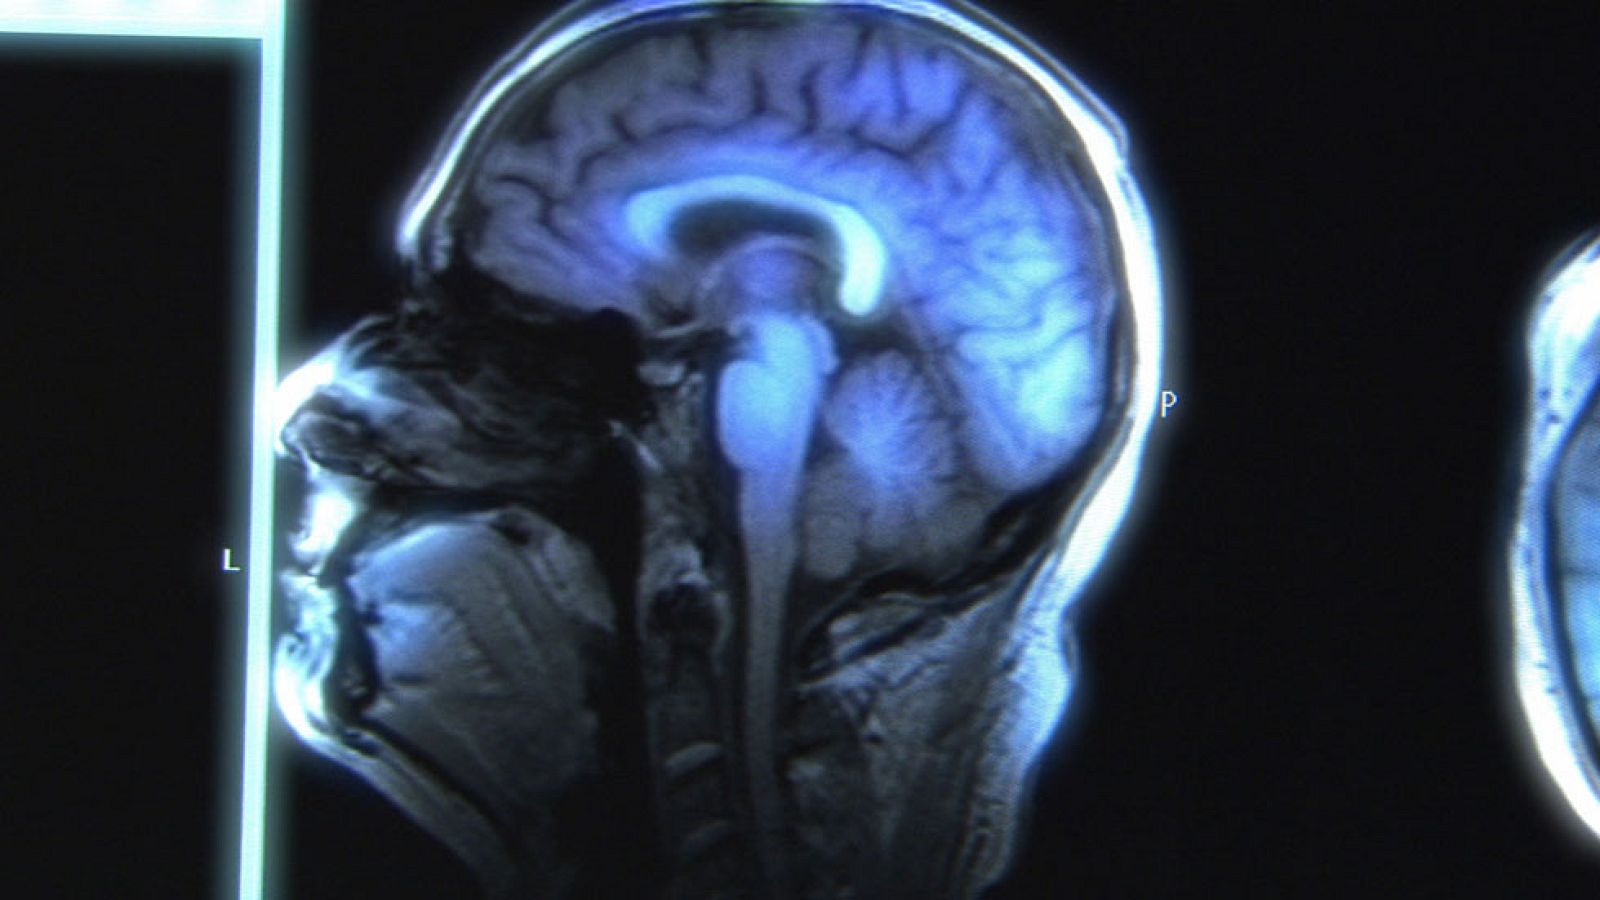

• Durante siglos se ha pensado que el cerebro adulto no podía cambiar. Pero ahora sabemos que el cerebro es plástico, es modificable.

El descubrimiento de la neuroplasticidad ha revolucionado la manera de entender el cerebro y ha abierto la puerta a nuevos tratamientos para enfermedades o trastornos mentales que pensábamos incurables como el trastorno obsesivo compulsivo, ictus, la esquizofrenia o el trastorno de estrés postraumático.

El descubrimiento de la neuroplasticidad es el descubrimiento de que nuestro cerebro puede modificar su estructura y su función a través de la experiencia mental solamente. La neurociencia en el pasado pensaba que el cerebro humano funcionaba igual que una máquina, si una parte se rompía era incapaz de funcionar bien, significaba que las personas que nacían con daños cerebrales o que sufrían daños cerebrales durante el crecimiento estaban condenadas a vivir con ello, puesto que las máquinas no son capaces de generar componentes nuevos ni de reorganizarse, pero gracias a la neurociencia sabemos que eso no es así.